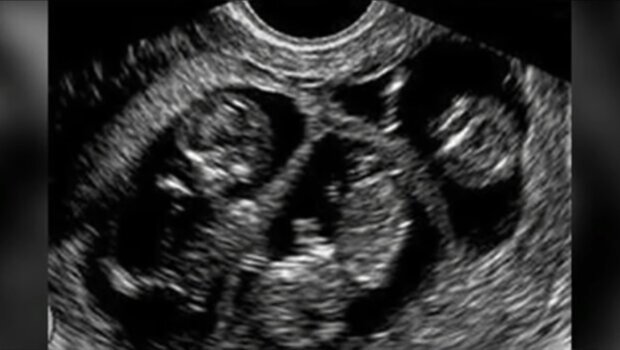

Ale los miał dla nich jeszcze jedną niespodziankę. Tydzień po adopcji Julia dowiedziała się, że jest w ciąży. Wiadomość ta wywołała u niej wiele emocji - radość, zaskoczenie, ale też nutkę niepewności. Czy jej już powiększona rodzina będzie w stanie poradzić sobie z dodatkową zmianą? Jak adoptowane dzieci zareagują na ciążę?